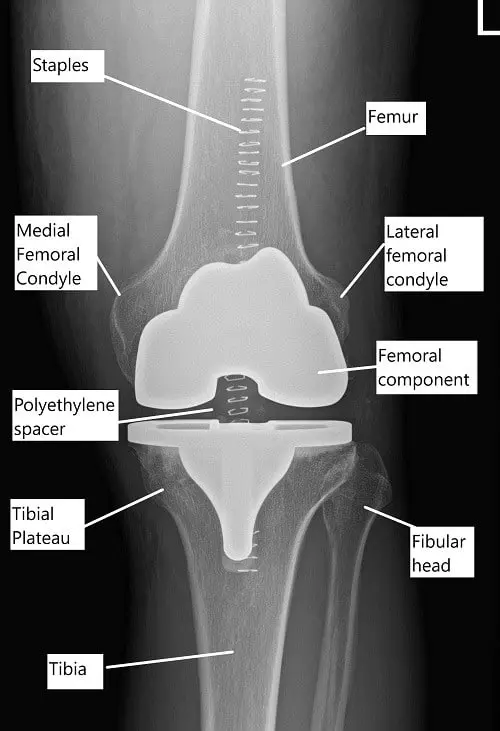

The knee joint is formed where the thigh bone, shin bone, and kneecap meet. Healthy cartilage allows these bones to glide smoothly. When cartilage wears away, the bones rub together and cause pain. Knee replacement restores a smooth surface so the knee can bend and straighten more easily.

Postoperative X-ray showing a total knee replacement.